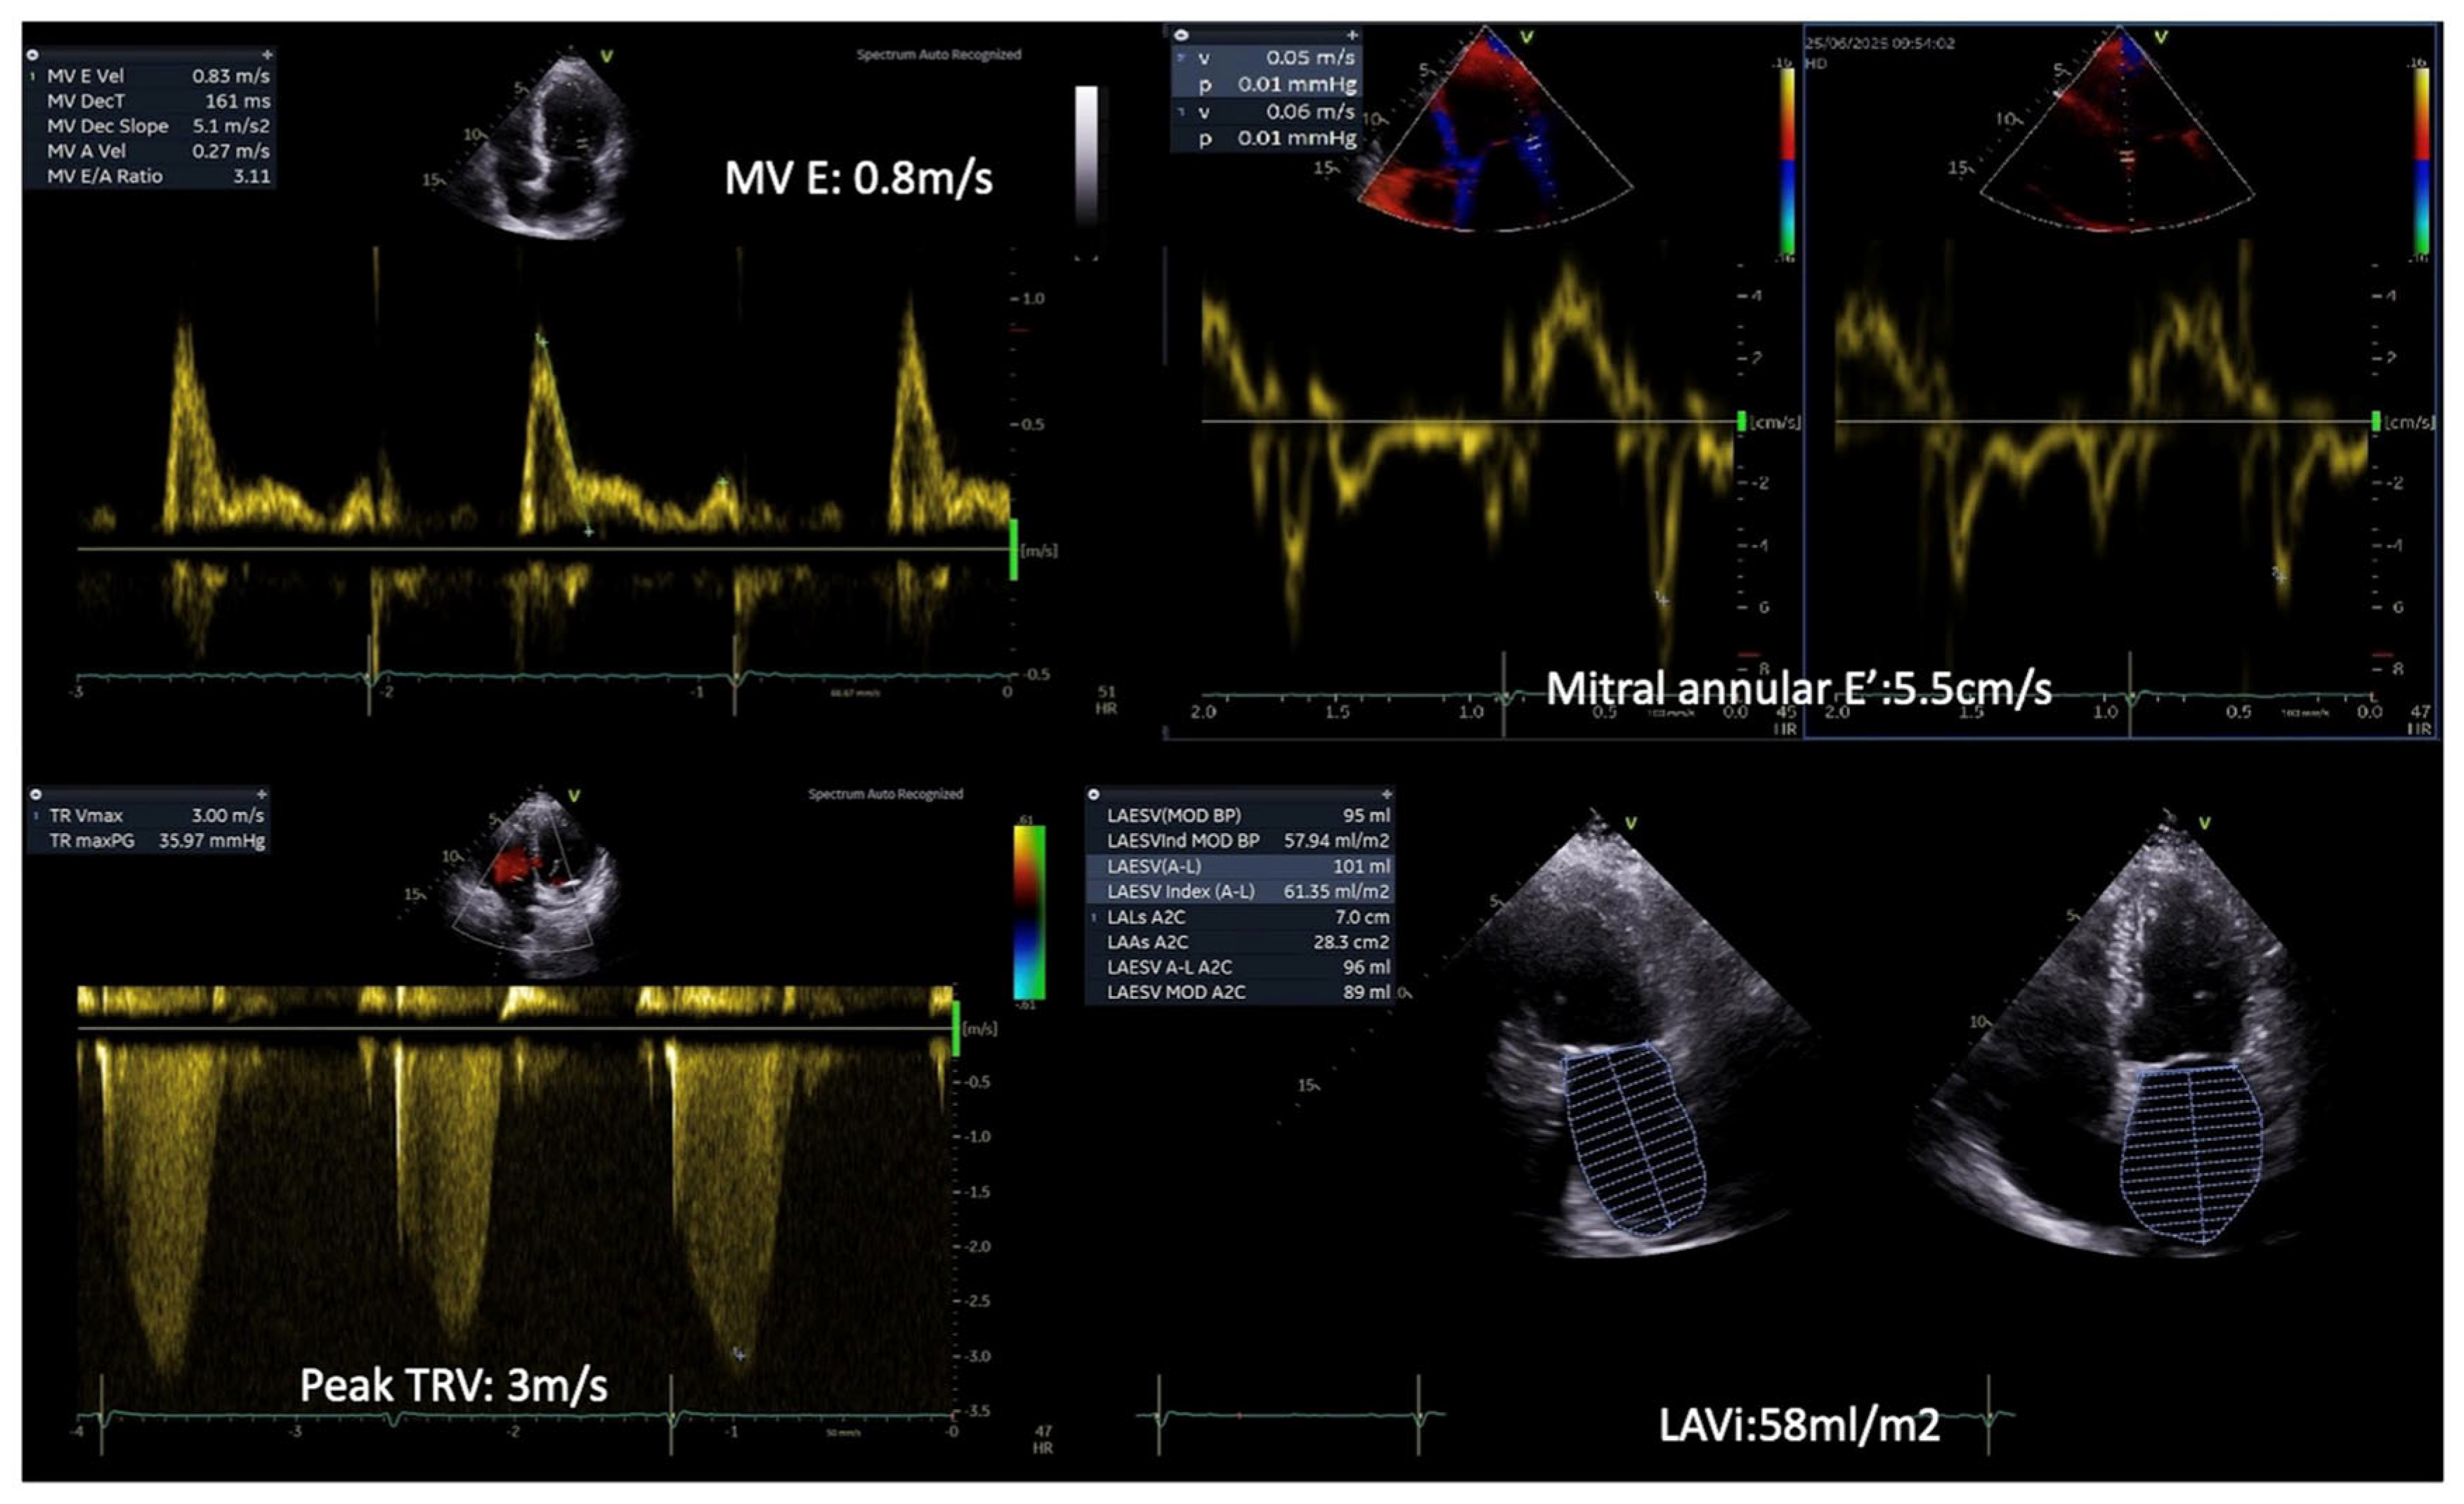

The key echocardiographic parameters of diastolic dysfunction include the transmitral E/A ratio, E/e’ ratio, early diastolic velocity (e’) using tissue Doppler imaging (TDI), left atrial (LA) volume index (LAVi), and the assessment of tricuspid regurgitation (TR) using Doppler ultrasound. The duration of uncontrolled DM correlates positively with the incidence and severity of diastolic dysfunction [40]. Jain et al. demonstrated a strong association between elevated hemoglobin A1C (HbA1c) levels and diastolic dysfunction. In their study, half of the participants with HbA1c >9.5% exhibited a restrictive filling pattern [43]. However, most studies report that DM patients with diastolic dysfunction present with impaired relaxation or pseudonormal filling patterns [38].

Initial studies showed decreased transmitral E/A ratio in patients with DM, even when LV mass remains normal [44]. The E/e’ ratio, which reflects LVFP, was found significantly elevated in patients with HbA1c levels ≥8.1% [40]. In agreement to previous studies, From et al. observed an independent association of DM duration of over four years with E/e’ > 15 [45]. Importantly, a septal E/e’ ratio >15 in diabetic patients is associated with the subsequent development of HF and increased mortality independent of CAD, HTN, or other echocardiographic parameters [46].

Current evidence suggests that LA dilatation may serve as a marker of diastolic dysfunction in diabetic patients [47]. The CARDIA (Coronary Artery Risk Development in Young Adults) study demonstrated that over a 5-year period, diabetes was not associated with either unindexed LA diameter or LA diameter indexed to body surface area (BSA) or height. However, after a 20-year follow-up period, a significant association emerged between diabetes and increased unindexed and indexed LA diameters [48]. Similarly, the TODAY (Treatment Options for Type 2 Diabetes in Adolescents and Youth) trial, reported that LA diameter, even when indexed for BSA or height, showed no correlation with poorly controlled DM [49]. These findings raise concerns about the utility of LA diameters as a reliable marker of DBCM [50].

The use of LA volumes has proven more effective in detecting subclinical cardiac damage in DM patients. Over the past decade, previous studies in DM patients have confirmed common LA enlargement, as measured by LA volumes and indexes [46,50,51,52]. Recent evidence highlights a strong association between disease duration and both increased LA volume and impaired LA function [50]. These parameters constitute independent predictors of cardiovascular events in diabetic patients [46,49,51,53,54]. Notably, an increased LAVi ≥ 32 mL/m2 has been identified as an independent and incremental predictor of cardiovascular morbidity and mortality in diabetic patients without known cardiovascular disease [55].

Diastolic dysfunction in individuals with DM is associated with a worse prognosis, as these patients face a higher risk of developing HF, compared to their counterparts without diastolic dysfunction [45]. Optimizing DM treatment and reducing HbA1c levels may lead to improvements in diastolic dysfunction, potentially delaying the progression to HF [56] (Figure 1).

During exercise, a rise in E/E′ and an increase in TR peak velocity (TRVpeak) are often observed in patients with HFpEF, reflecting an abnormal surge in LVFP and PASP, respectively. As heart rate rises, the impaired relaxation in diabetes leads to a disproportionate rise in LVFP and pulmonary pressures, exposing diastolic abnormalities not evident at rest [91,92,93]. Notably, according to the ESC consensus criteria, an exercise E/e′ ≥ 15 and/or TRVpeak > 3.4 m/s are indicative of HFpEF during stress [90]. Moreover, ESE may show an inadequate increase in stroke volume despite rising LVFP, differentiating cardiac limitations from non-cardiac causes of exercise intolerance (Figure 6).